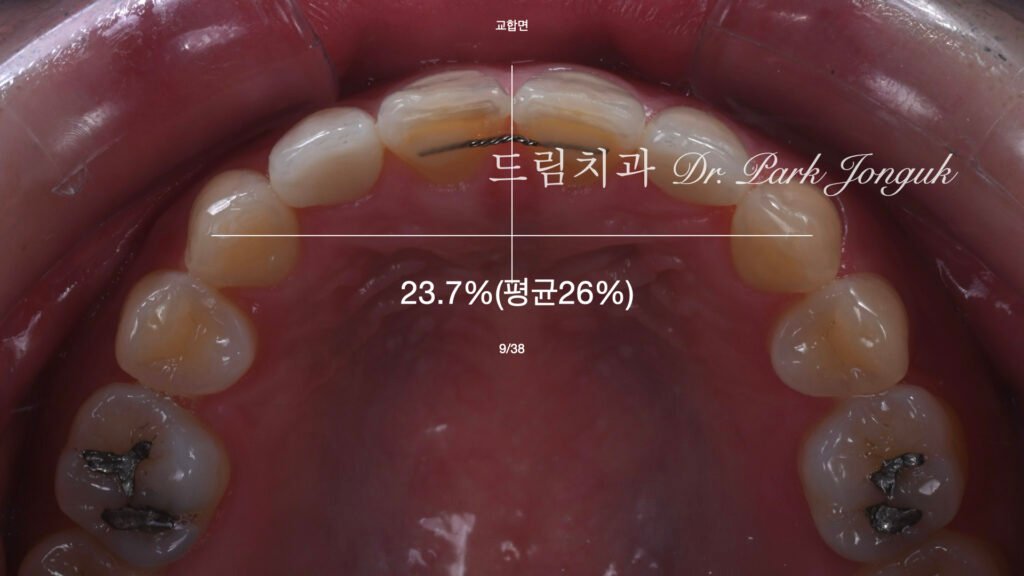

2.2 안면 분석 기반의 미소 설계 (사진 3~6)

[사진 3, 4, 5, 6 참조] 저희는 단순히 치아만 보지 않습니다. 모든 설계는 안면 분석(Facial Analysis)에서 시작됩니다. * Incisal Edge Re-design: 옥니 개선을 위해 치아의 길이를 연장하고 전방 볼륨을 부여하는 계획을 세웠습니다.

- Diagnostic Wax-up: 디지털 분석 데이터를 바탕으로 왁스 모델을 제작하여, 최종 결과물이 입술 라인과 이루는 조화를 미리 검증했습니다.

4. 핵심 기술: 보철물 간의 색상 매칭 (Shade Matching)

가장 큰 기술적 도전은 **’크라운과 라미네이트의 색을 똑같이 맞추는 것’**이었습니다.